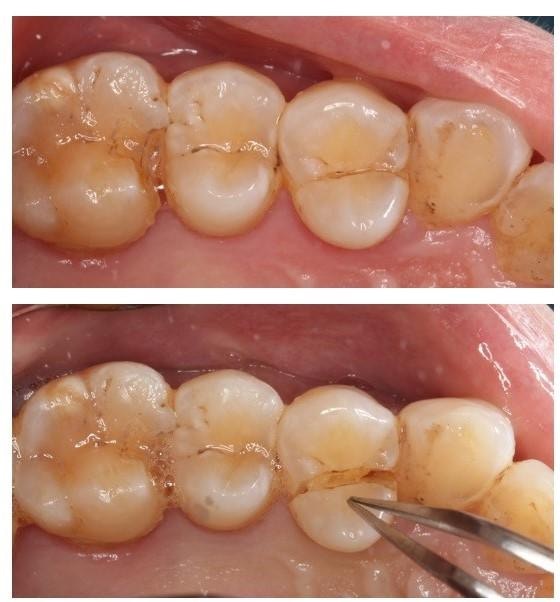

當牙醫懷疑病人牙齒有裂,會進行不同的詳細檢查。例如先以排除法檢查相關牙齒有否蛀牙或牙周病等其他問題,再慢慢收窄範圍,接着以咬合測試(Bite test)或透照法檢查 (Transillumination),嘗試找出裂牙所在位置。

牙醫會以照X光片和臨床病徵,判斷裂牙的術後情況(Prognosis),與病人討論不同的治療方案。舉例當牙齒裂紋並沒有裂愈深,裂向牙房神經線,而剩餘的牙齒結構完整,牙醫會嘗試以補牙物料或牙套修復及保護牙齒。但如果裂紋已經深入牙房神經線,就有需要先進行根管治療,然後才可進行修復。再者,如果裂紋已裂到牙齒深處,例如裂到牙肉以下或者牙房底部,情況便不容樂觀,牙醫會與病人討論牙齒的去留,可能有需要拔牙。